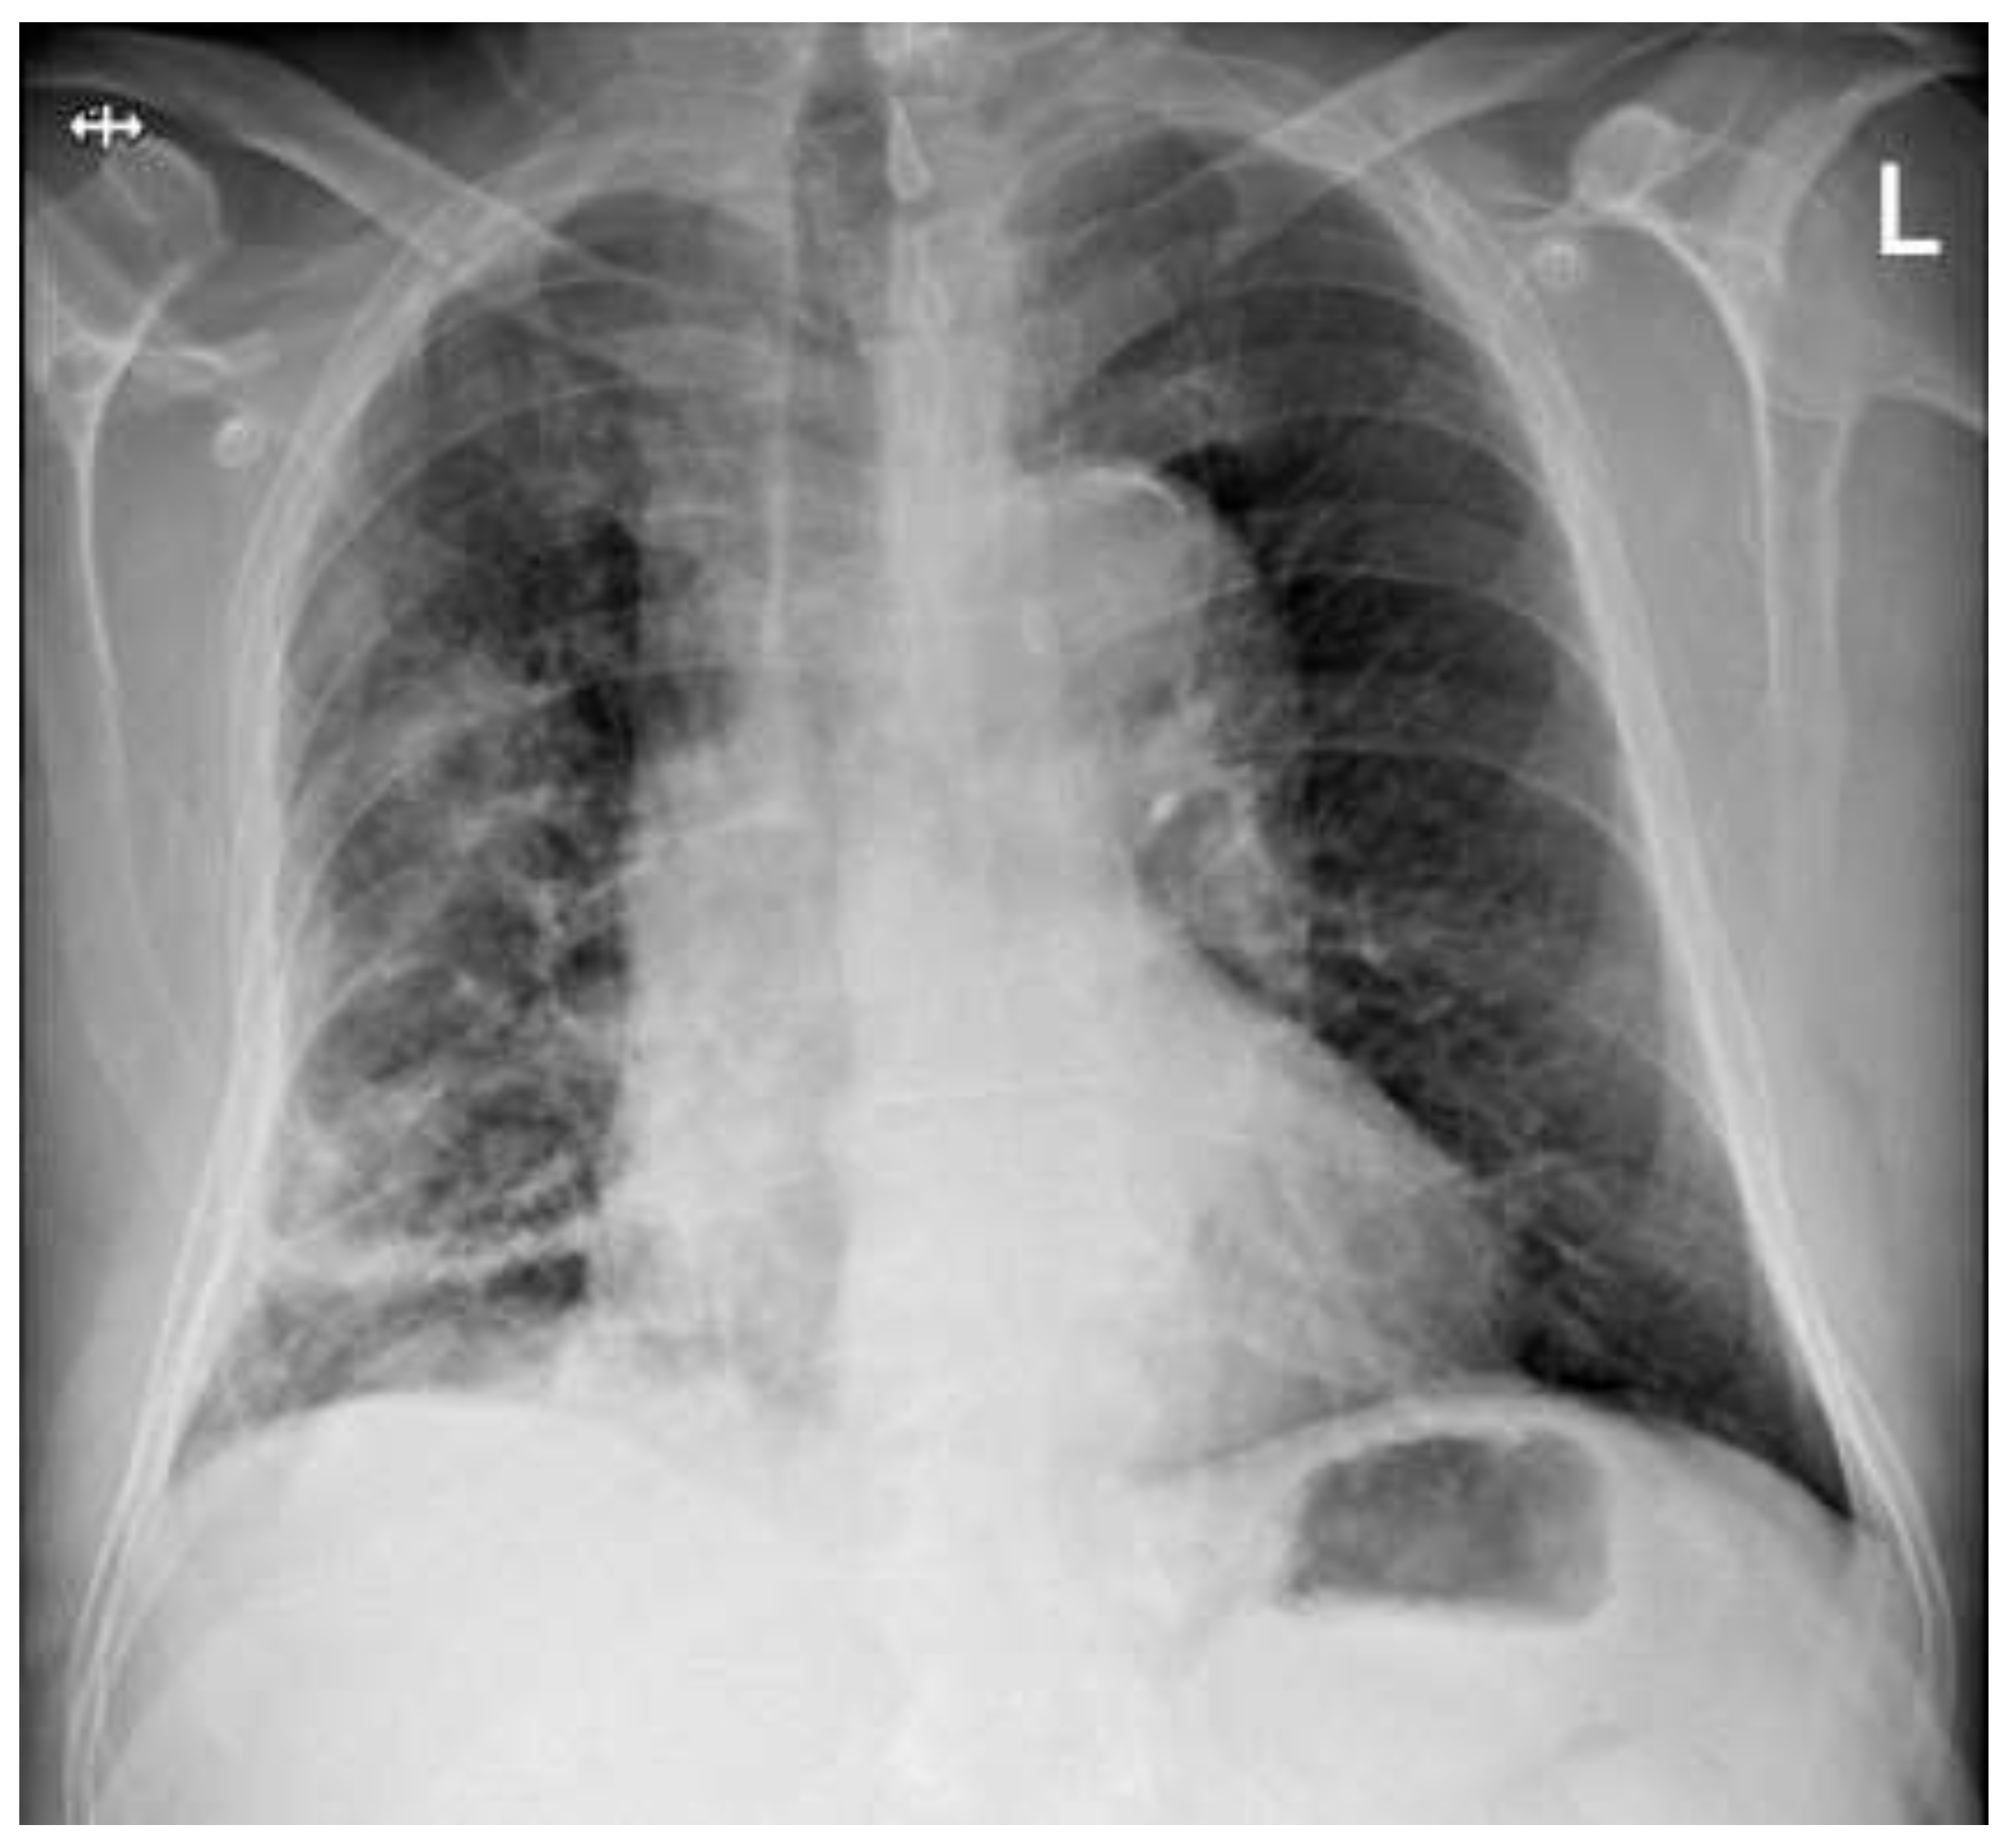

A follow-up BGA documented a significant improvement in gas exchange with reduced oxygen supply. Also, the chest radiograph (Figure 4), performed before discharge, showed almost a full resolution of the consolidation. The patient was finally discharged on day 20 in a good general condition.

Figure 3. Follow-up chest X-ray (Day 15 post treatment initiation). The chest radiograph shows substantial improvement compared to Figure 1 and Figure 2. There is significant aeration of the right lung with the resolution of the pleural effusion, though residual opacities persist in the right lower zone.